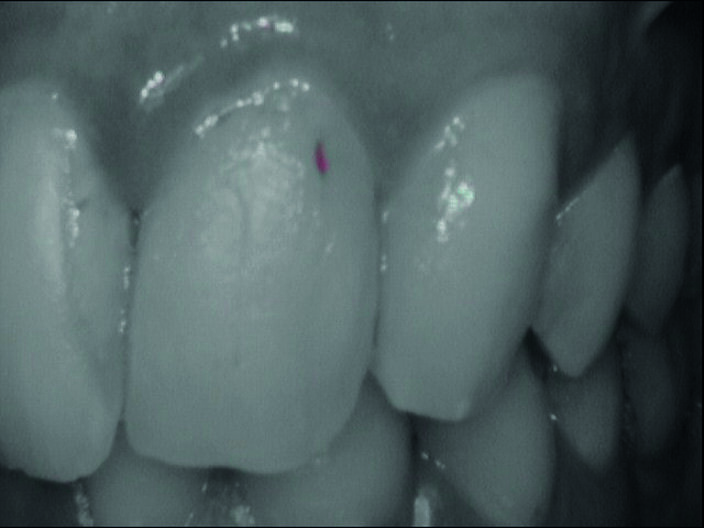

Durante l’esame obiettivo (Figg. 1a, 1b) rileviamo il danno iatrogeno da terapia ortodontica precedente alla visita e riscontriamo la presenza di processo carioso ICDAS 3 in zona 33 e in zona 47, white spots in zona 31 e 41. Durante l’esame obiettivo, l’ausilio della videocamera intraorale Sopro-Care (Acteon) permette, tramite filtri appositi, di evidenziare in modo rapido e accurato le zone di demineralizzazione e le aree infiammate e di mostrarle al paziente in real time, rendendolo attivamente partecipe e consapevole della situazione clinica (Figg. 2a-2f). I ricercatori del Baylor College of Dentistry hanno dimostrato che il 23,4% dei pazienti ha sviluppato almeno una white spot lesion durante il trattamento ortodontico.

Chiediamo al paziente se si fosse sottoposto a terapia ortodontica e il paziente riferisce di essersi sottoposto a terapia ortodontica in età adolescenziale per circa 2 anni e di non aver dato molta importanza alle lesioni presenti, poiché non aveva avuto grande sintomatologia riteneva che le white spots presenti non fossero un segno di demineralizzazione. Alla domanda della causa delle lesioni riferiamo che un inefficace controllo di placca domiciliare e uno stile di vita alimentare cariogeno, alzava il rischio di demineralizzazione delle lesioni che probabilmente erano state provocate dall’apposizione delle bande ortodontiche con materiale non di ultima generazione come i cementi vetroionomerici in grado di liberare fluoro. Inoltre riferiamo che durante la fase terminale del debonding, la topografia delle lesioni faceva presupporre l’uso poco attento di frese che avevano danneggiato lo smalto. Il paziente si mostra motivato e chiede una soluzione terapeutica che abbia come obiettivo la risoluzione funzionale ed estetica più veloce possibile. Viene condiviso con il paziente il piano terapeutico e proponiamo di iniziare con la terapia parodontale non chirurgica. Concordiamo con il paziente tempi, modalità di utilizzo e strumenti per migliorare il management degli stili di vita domiciliari, per il controllo chimico e meccanico del biofilm batterico (Nardi GM, Sabatini S, Guerra F, Tatullo M, Ottolenghi L. Tailored Brushing Method (TBM): an innovative simple protocol to improve the oral care. J Bio- med 2016; 1:26-31).